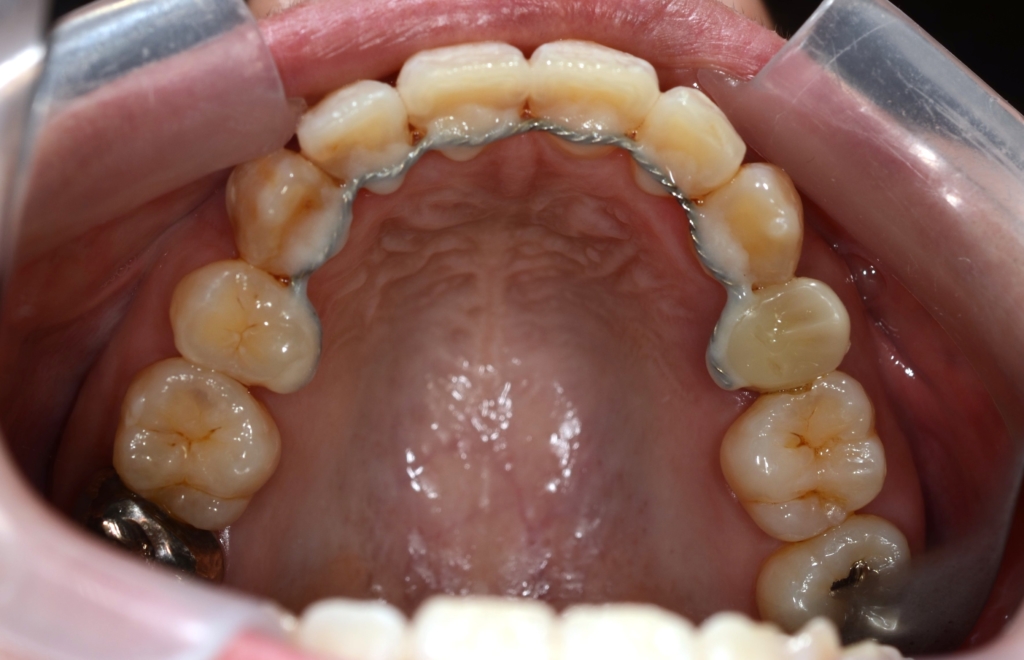

マルチブラケットシステム(ハーフホワイトtype)で矯正を開始。

*ハーフホワイトtype:上下とも歯の表側に白いブラケットを付けて、上には白いワイヤー&下には銀色のワイヤーを用いたストレートワイヤーによる歯列矯正

【保定】 上下ともフィックスタイプ&クリアリテーナー